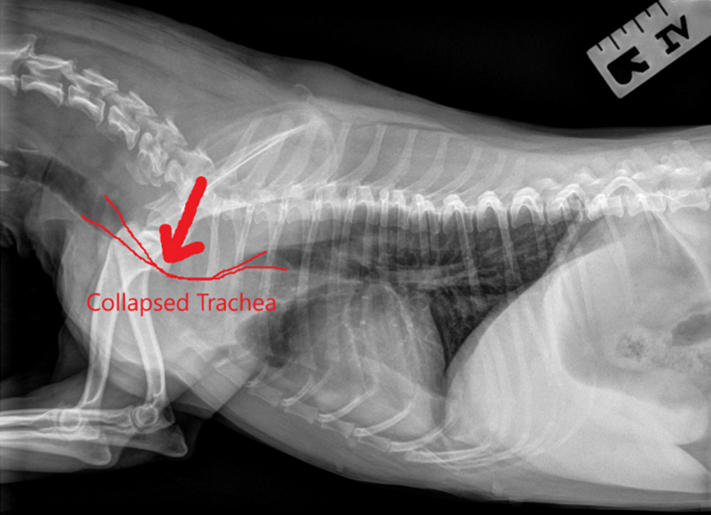

흉부 방사선(X-ray) 검사에서 흡기와 호기 시 촬영을 비교하여 기관이 좁아지는 모습을 확인하게 됩니다.